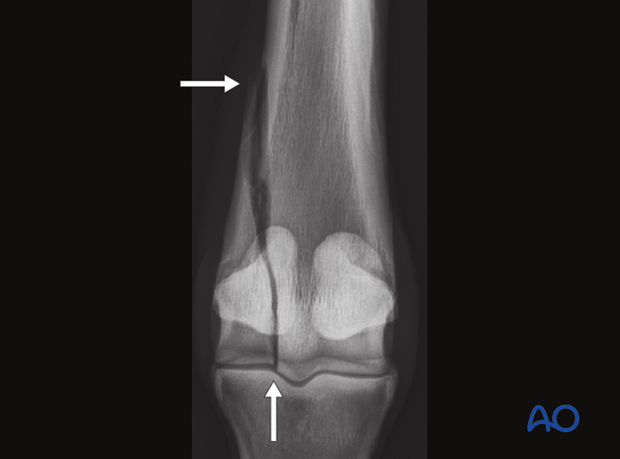

A full set of metacarpo/metatarsophalangeal joint radiographs should be taken as well as the tangential view silhouetting the distal palmar/plantar third metacarpal/metatarsal bone. The fracture is easily identified on the straight dorsopalmar/plantar projection, but the additional view is necessary to adequately evaluate the joint.

Recognition of comminution along the distal palmar/plantar margin of the bone is important in giving a preoperative prognosis.